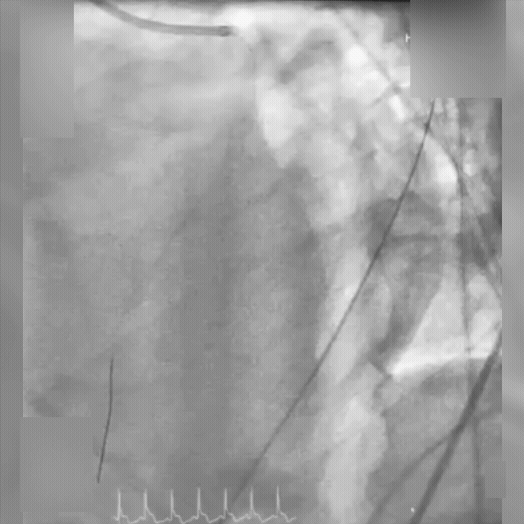

Dr. Hust completed two thrombectomy passes with CAT RX, removing approximately 95% of the thrombus. With the use of intravascular ultrasound, stents were successfully implanted into the culprit artery. The patient was also noted to have severely reduced left ventricular function and hypotension. The patient was placed on vasopressors and inotropic support via intravenous infusions and ultimately, mechanical circulatory support via an Impella device.

LAD angiography status-post aspiration thrombectomy with CAT RX and stent implantation in the offending LAD lesion. LAD angiography status-post aspiration thrombectomy with CAT RX and stent implantation in the offending LAD lesion.

Video: LAD angiography status-post aspiration thrombectomy with CAT RX and stent implantation in the offending LAD lesion.